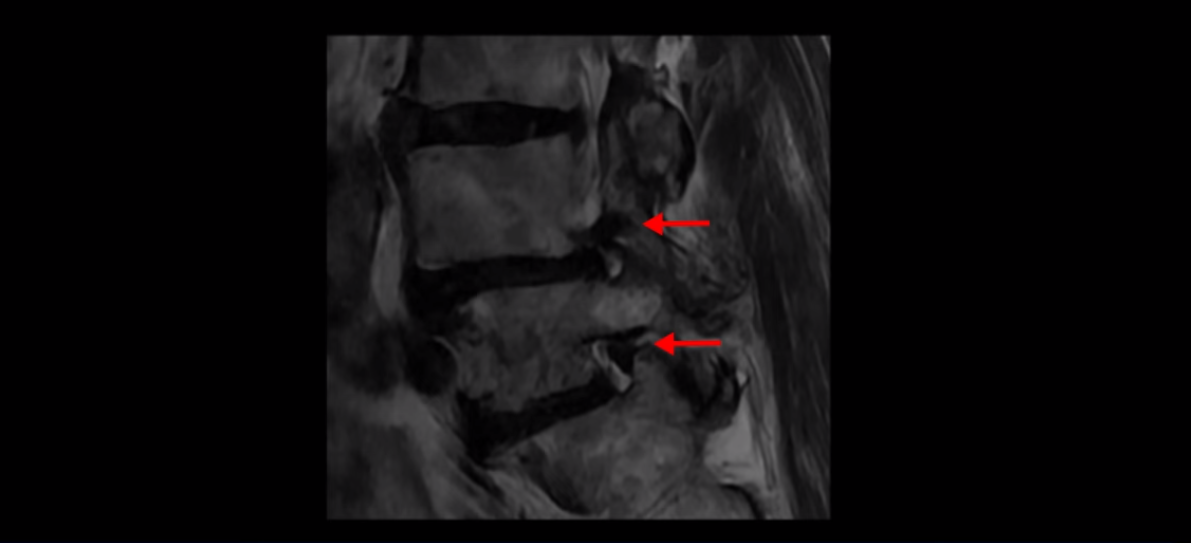

제가 먼저 이분 MRI를 보고 설명해 드린 후 어떻게 이런 분들을 수술 없이 허리 기능재활치료로 호전시킬 수 있는지 자세히 설명드리겠습니다. 이분 허리가 보시다시피 여러 마디가 퇴행되어 있고

4번 5번에는 뼈가 밀려 나간 전방전위증도 있습니다.

4번 5번 마디를 자세히 보면 심한 중심성 협착이 있어서 신경 구멍이 매우 좁아져 있습니다.

또 신경 가지가 빠져나가는 추간공도 매우 좁아져 있습니다.